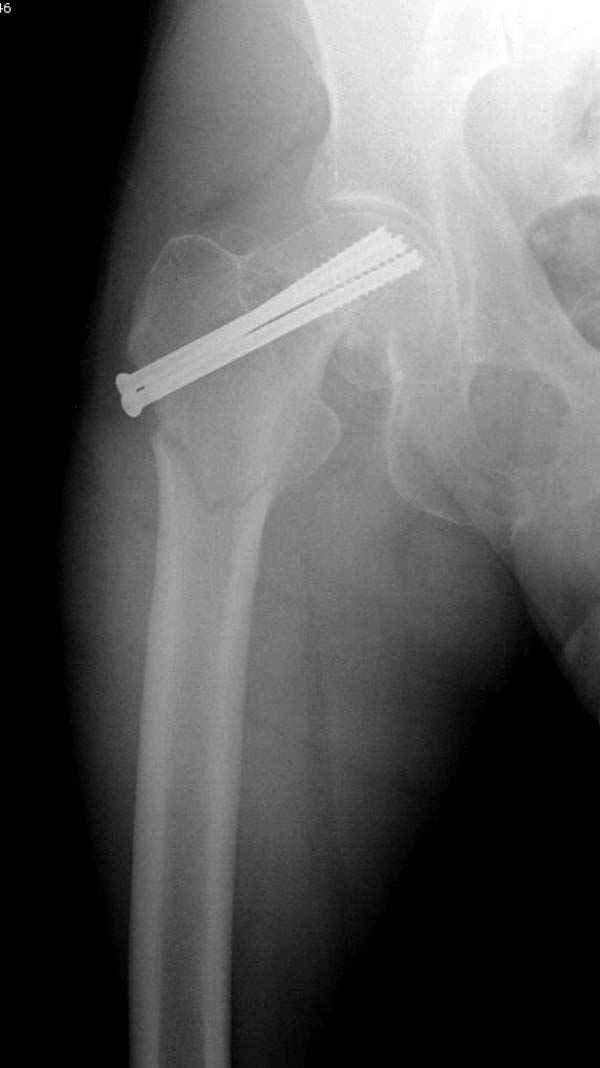

в течение первых 72 часов после перелома, остеосинтез тремя спонгиозными шурупами.

Почему неполный перелом? Я бы назвал его вколоченным!

Перелом конечно не вколоченный т.к. видно линию перелома и нет суперпозиции костной ткани.

Профилактику дальнейшего раскола неполного перелома шейки провели тремя канюлированными шурупами.